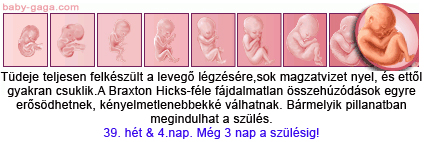

Tegnap UH vegyes érzésekkel telt. Luca/Máté teljesen egészséges végtagilag és belszervileg is. Méretei megfelelőek.

A becsült súlyáról nem kaptam információt. Kb. egy pohár joghurttal lehet most egyenlő.

Viszont nálunk az a legújabb, hogy a 18. és a 20. héten is van uh, és két különböző orvosnak kell néznie. Megbeszéltük a dokimmal, hogy a 18. heteset más csinálja majd. Tegnap egy profi uh-s doki volt, még örültem is. Nadehát a modora!!!????? Tudtam, hogy fapofa, de évek óta nem találkoztam vele. Először is nem jöhetett be a férjem. Másodszor én sem láthattam a babát. Harmadszor még le is tolt, hogy korán jöttem, később jobban lehet látni, ha gond van. Nehát kinyílt a bicska a zsebemben! Közöltem vele, hogy a 20. héten is kell jönni, akkor most éppen jókor vagyok itt. Erre azt mondta, hogy hülyeség, majd úgyis megváltoztatják. Dilííís!

Utána mentem a dokimhoz. Jól kibeszéltük a témát. Közben megnézett. Éreztem, hogy valami nincs rendben odalent, de az utróra fogtam egy ideig, majdcsak helyreáll. Különösebben nem okozott gondot, csak kellemetlen volt időnként. Hát kiderült, hogy gombás jellegű fertőzés, kaptam kúpot, 6 nap, és rendbejövök. Méhszáj teljesen zárt.